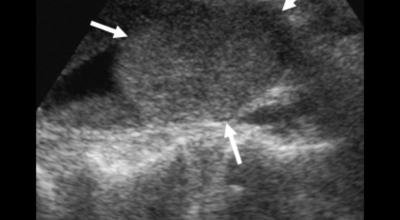

오른쪽 갈비뼈 아래와 옆구리 통증으로 인해 병원을 방문하였다가 복부 초음파를 통하여 ‘급성 담낭염’ 진단을 받는 경우가 있답니다. 담낭 질환도 1개입니다. 급성 담낭염의 경우 CT, MRI와 같은 검사보다 복부 초음파로 검사하는 것이 정확도가 상대적으로 높는 것으로 알려져 있어요. 담낭은 간의 아래쪽 경계면에 위치하고 있고 급성 담낭염이란 담낭 내 담즙이 비워지지 않을 경우 발생하는 질환으로 담낭 내부에 있는 돌인 ‘담낭결석’과 90% 이상 관련이 되어 있답니다.

이 결석이 담낭 내 담즙이 지나가는 통로를 막고 있으므로 담즙이 소장으로 흘러가지 못하게 되고 이에 따라 감염이 발생해 증상이 나타날 수 있답니다. 담낭염은 복부 초음파로 알 수 있는 것이므로 증상이 나타나면 검사를 받아볼 수 있답니다. 복부 위에 통증이 간헐적으로 발생하고 시간이 지날수록 열과 오한이 동반된다면 의심해 볼 필요가 있어요. 복부 초음파로 통해 ‘담낭결석’을 확인할 수 있을 뿐만 아니라담낭의 크기와 담낭 벽의 두께까지 알 수 있기 때문에 정확한 상태를 관찰할 수 있어요.